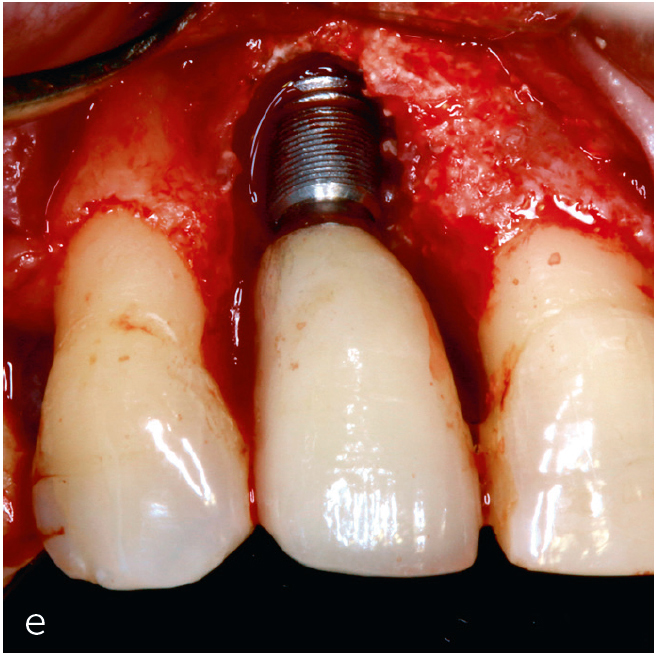

Abb. 3a bis h Falldokumentation mit Zustand nach Implantation und lateraler Augmentation alio loco: a) klinische Ausgangssituation mit Fistelung vestibulär in der Region 12; b) klinische Parameter (PI=Plaque Index 1-3, ST=Sondierungstiefe, MR=Mukosarezession, KM=keratinisierte Mukosa, BOP=Bleeding on probing, SUPP=Suppuration); c) radiologische Ausgangssituation mit initialem periimplantären Knochenabbau; d) operativer Zugang; e) Defektdarstellung nach Entfernung des periimplantären Entzündungsgewebes; f) Defektaugmentation mit einem Gemisch aus Eigenknochen und xenogenem Knochenersatzmaterial; g) Kollagenmembran; h) das aus dem Gaumenbereich entnommene Bindegewebstransplantat (BGT).